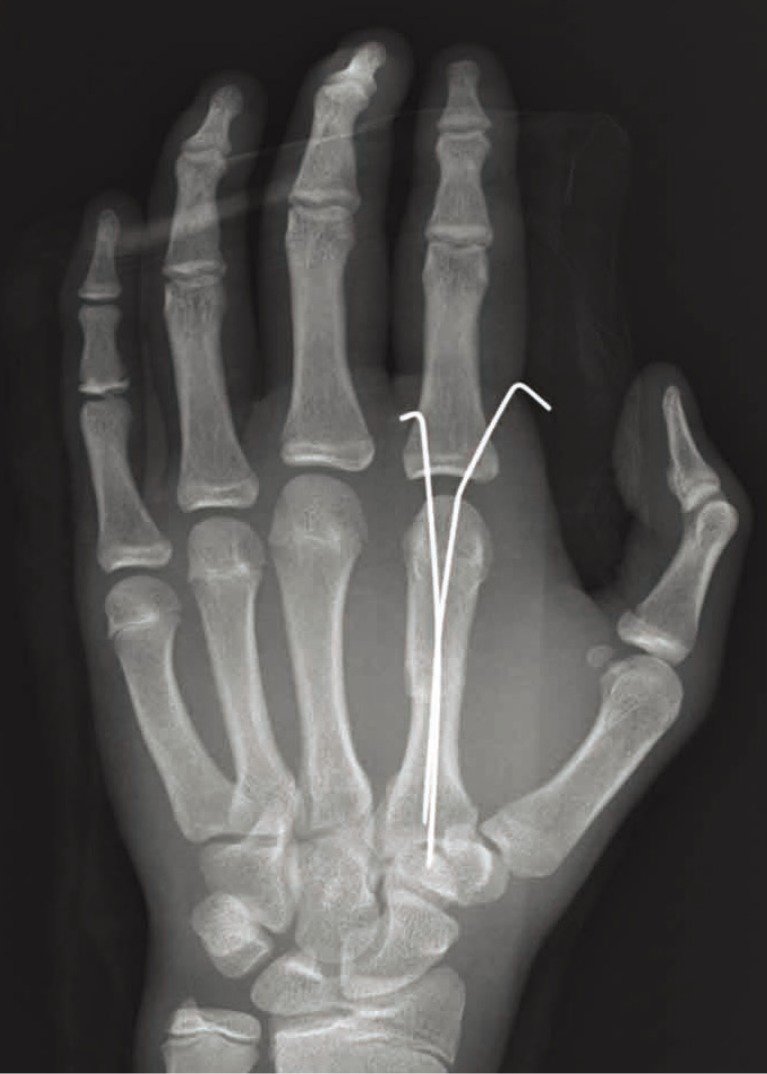

A Kirschner wire (also called a K-wire) is a thin, flexible wire made of stainless a available in various diameters. The wires can be smooth or threaded (the latter arc used in situations in which backing out of the pin is undesirable).

2. Definite fixation – with small fracture fragments (e.g. wrist fracture, hand injuries).